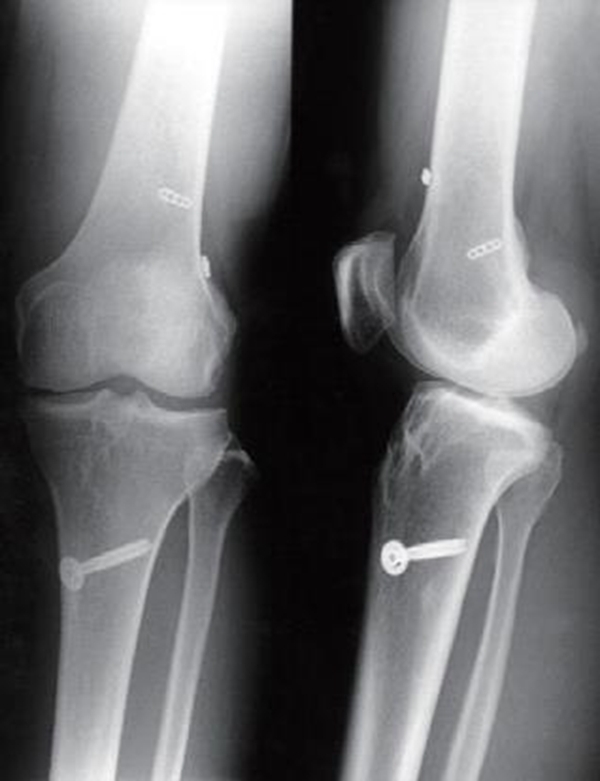

早期的ACL四骨道双束重建技术几乎是传统单束重建的翻版(图5)。可以说是在传统单束重建的基础上在术者认为合适的位置增加了后外束。该技术还不能称之为解剖双束重建,只能称之为非解剖双束重建技术。

图5 最早的四骨道双束重建术术后影像

前内束股骨骨道定位几乎就是传统ACL单束重建,该双束重建将前内束的股骨骨道定位在过顶位,超过12点的位置;后外束的股骨骨道定位在超过12点的位置。前内束的胫骨骨道用55°的定位器定位在足印区中心点,后外束胫骨骨道在保留3mm骨桥基础上定位在前内束胫骨骨道的后外侧。